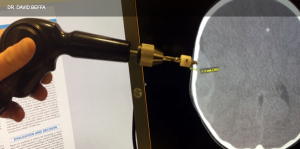

Figure 1. Measure the skull thickness on CT to set stopper depth on the Integra skull trephination kit with adjustable stopper.